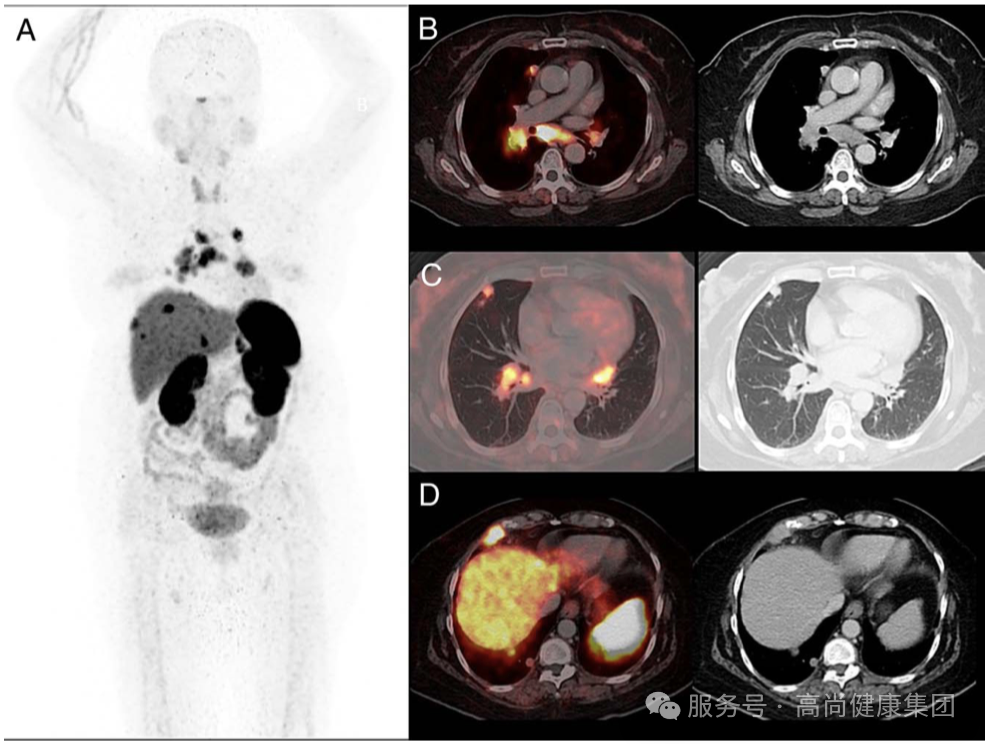

(A,B)68 Ga--DOTA-TATE 显示多发的 DOTA-TATE 摄取增高的淋巴结转移瘤,分布于纵膈、内乳区、双肺门、横膈上及肋间区;

(C)双肺多发结节,摄取程度不一;

(D)右侧胸膜转移瘤。患者左侧腮腺放疗后未见 DOTA-TATE 摄取增高,提示治疗有效。该病例提示:腮腺淋巴上皮癌患者中的 SSTR-2 可以作为 PET/CT 成像的分子标记物。[3]